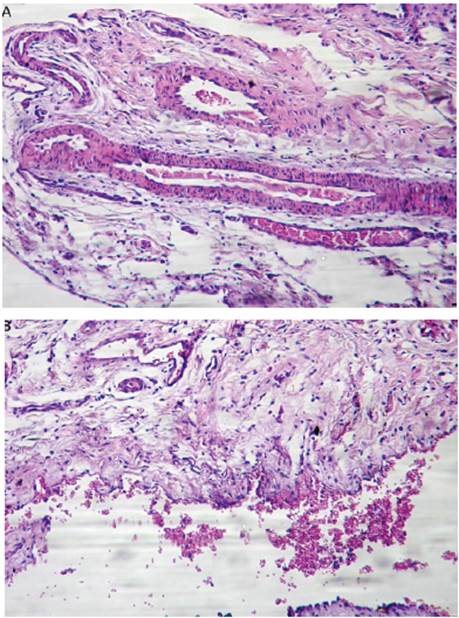

Diffuse mononuclear infiltrate was observed in the lamina propria, blood vessels, and lumen of the oviducts of inoculated heifers. Furthermore, at days 40, and 55 post- infection (p.i.), the oviducts showed pronounced vascularization (Figure 1A) and presence of lymphocytes and erythrocytes in the lumen (Figure 1B).

Figure 1 A. Oviduct of a heifer at day 40 p.i. showing pronounced vascularization (10X). B. Oviduct of a heifer at day 40 p.i. showing presence of lymphocytes and erythrocytes in the lumen (10X).